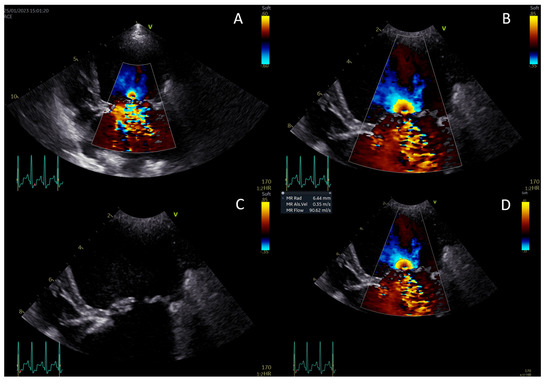

2.2. Echocardiography